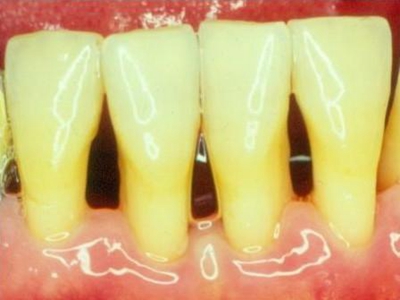

牙龈退缩露出淡黄色牙根图

牙龈退缩患者的牙龈退缩后,淡黄色牙龈明显露出。若进一步发展,易使对应位点的牙槽骨发生骨吸收,可能诱发龋齿、牙龈敏感、菌斑堆积等。